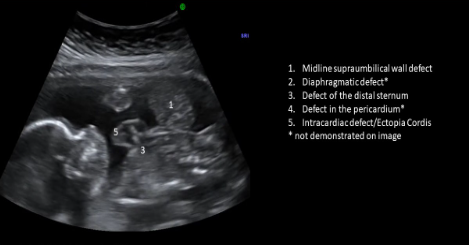

Pentalogy of Cantrell

Midline supraumbilical wall defect

Diaphragmatic hernia

Defect of distal sternum

Defect in pericardium

Intracardiac defect/ectopia cordis